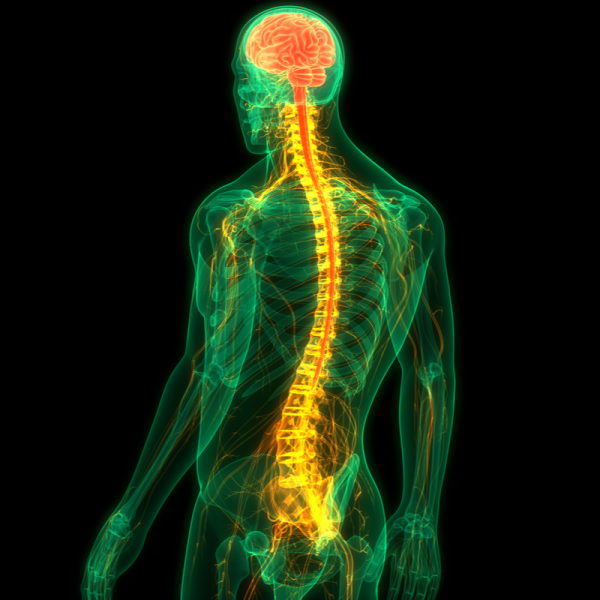

Benign tumours and frequency therapy

Being diagnosed with a benign tumour can be a frightening experience for many people.

Although, unlike malignant tumours, this type of tumour is not life-threatening, it can still lead to unpleasant symptoms and limitations.

Fortunately, there are many different treatment options available today that can help shrink or even completely remove benign tumours.

One relatively new method that is gaining more and more attention is frequency therapy.

This treatment method uses electrical impulses to inhibit tumour growth and strengthen the immune system.

In this article, we will take a closer look at benign tumours and frequency therapy and explain how this innovative form of therapy can help to reduce the effects of tumours.